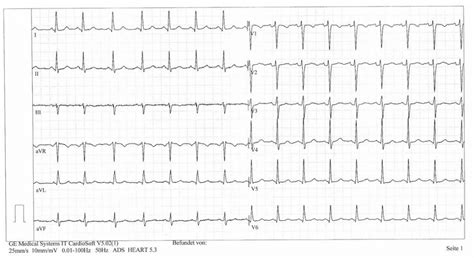

3. Elektrokardiografické vyšetrenie (EKG)

EKG sa indikuje u:

- Dospelých nad 40 rokov, alebo u mladších pacientov s prítomnosťou rizikových faktorov srdcovocievnych ochorení.

- Detí s príznakmi a ťažkosťami srdcových ochorení.

EKG by nemalo byť staršie ako 14 až 28 dní pred plánovanou operáciou, v niektorých prípadoch dokonca len 2 týždne.